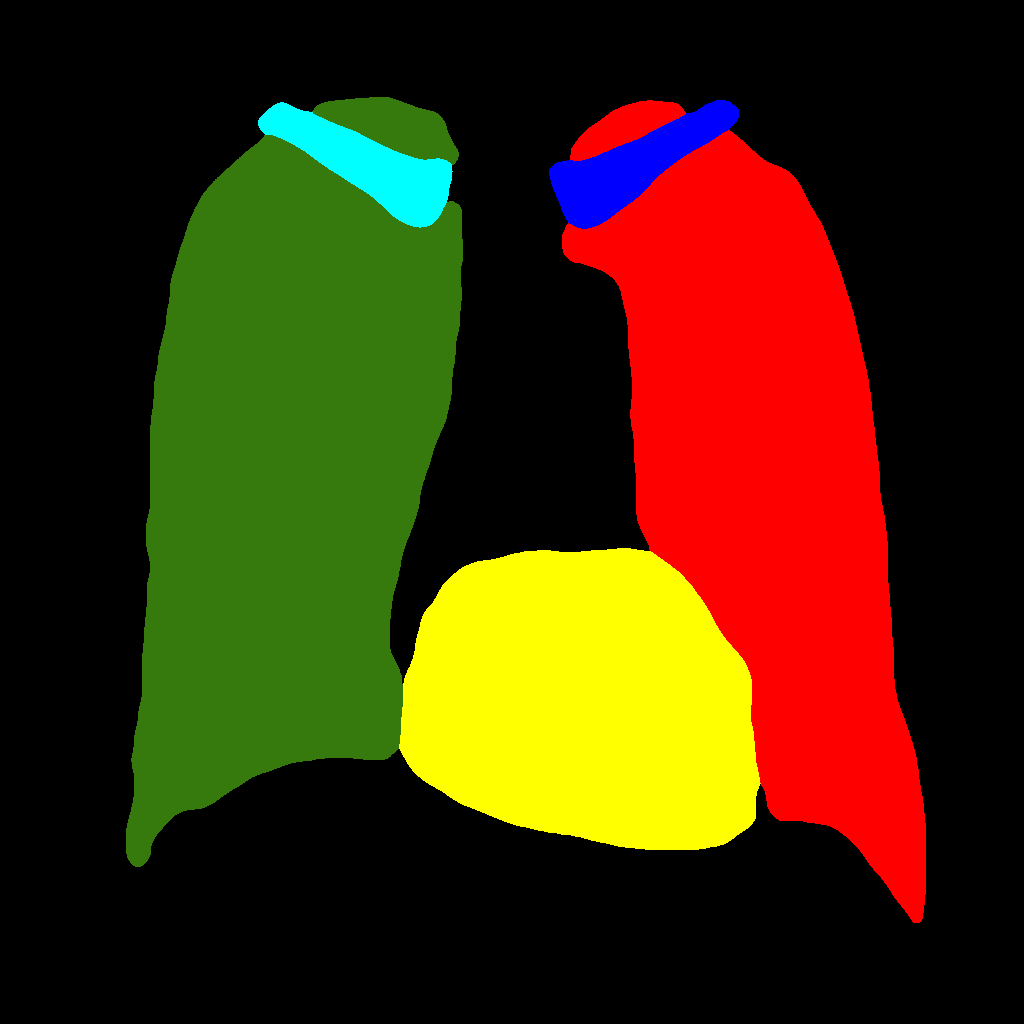

In this section, some examples of images and corresponding segmentations, generated with the approaches described in Section 3, are qualitatively examined. We also report some comments from three physicians on the generated segmentations, to provide a medical assessment of the quality of our method.

Figure 5 and Figure 6 display some examples — randomly chosen from all the generated images — of the label–maps and the corresponding chest X–ray images generated with the three methods described in Section 3, using the FULL_DATASET and the TINY_DATASET, respectively. We can observe that, with the single and two–stage methods, the images tend to be more similar to those belonging to the training set. For example, in most of the generated images there are white rectangles, which resemble those present in the training images, used to cover the names of both the patient and the hospital. Instead, the three–stage method does not produce such artifacts, suggesting that it is less prone to overfitting.

Moreover, in order to clarify the limits of the three–stage method, we assessed the quality of the segmentation results based on three human experts, who were asked to check 20 chest X–ray images, along with the corresponding supervision and the segmentation obtained by the SMANET network. Such images were chosen among those that can be considered difficult, at least based on the high error obtained by the segmentation algorithm. Figure 7 and Figure 8 show different examples of the images evaluated by the experts. The first column represents the chest X–ray image, while the second and the third columns, whose order was randomly exchanged during the presentation to the experts, represent the target segmentation and our prediction, respectively. The three physicians were asked to choose the best segmentation and to comment about their choice. Apart from a general agreement of all the doctors on the good quality of both the target segmentation and the segmentation provided by the three–stage method, surprisingly, they often chose the second one. For the examples in Figure 7, for instance, all the experts share the same opinion, preferring the segmentation obtained by the SMANET over the ground–truth segmentation. To report the results of the qualitative analysis, we numbered the target and predicted segmentation with 1 and 2, respectively, while doctors were assigned unordered pairs to obtain an unbiased result. Then, with respect to Figure 7(a), the comments reported by the experts were: 1) In segmentation 1, a fairly large part of the upper left ventricle is missing; 2) I choose the segmentation number 2 because the heart profile does not protrude to the left of the spine profile; 3) The best is No. 2, the other leaves out a piece of the left free edge of the heart, in the cranial area. Instead, for Figure 7(b), we obtained: 1) The second image is the best for the cardiac profile. For lung profiles, the second image is always better. The only flaw is that it leaks a bit on the right and left costophrenic sinuses. 2) Image 2 is the best, because the lower cardiac margin is lying down and does not protrude from the diaphragmatic dome. Image number 1 has a too flattened profile of the superior cardiac margin. 3) No. 2 for the cardiac profile more faithful to the real contours.

Instead, they reported conflicting opinions or decided not to give a preference with respect to the examples in Figure 8. When they agreed, they generally found different reasons for choosing one segmentation over the other. With respect to Figure 8(a) the comments reported by the experts were: 1) I prefer not to indicate any options because the heart image is completely subverted; 2) Segmentation number 2 is better, even if it is complicated to read because there is a “bottle–shaped” heart. The only thing that can be improved in image 2 is that a small portion of the right side of the heart is lost; 3) No. 1 respects more what could be the real contours of the heart image. Instead, for Figure 8(b) we obtained: 1) I prefer No. 2 because the tip of the heart is well placed on the diaphragm and does not let us see that small wedge–shaped image that incorrectly insinuates itself between heart and diaphragm in image 1 and which has no correspondence in the RX; 2) Both are good segmentations. Both have small problems, for example: in segmentation 1 a small portion of the tip (bottom right of the image) of the heart is missing, in segmentation 2 a part of the outflow cone (the “upper” part of the heart) is missing. It is difficult to choose, probably better No. 1 because of the heart; 3) No. 2 because No. 1 carnally probably exceeds the real dimensions of the cardiac image, including part of the other mediastinal structures.